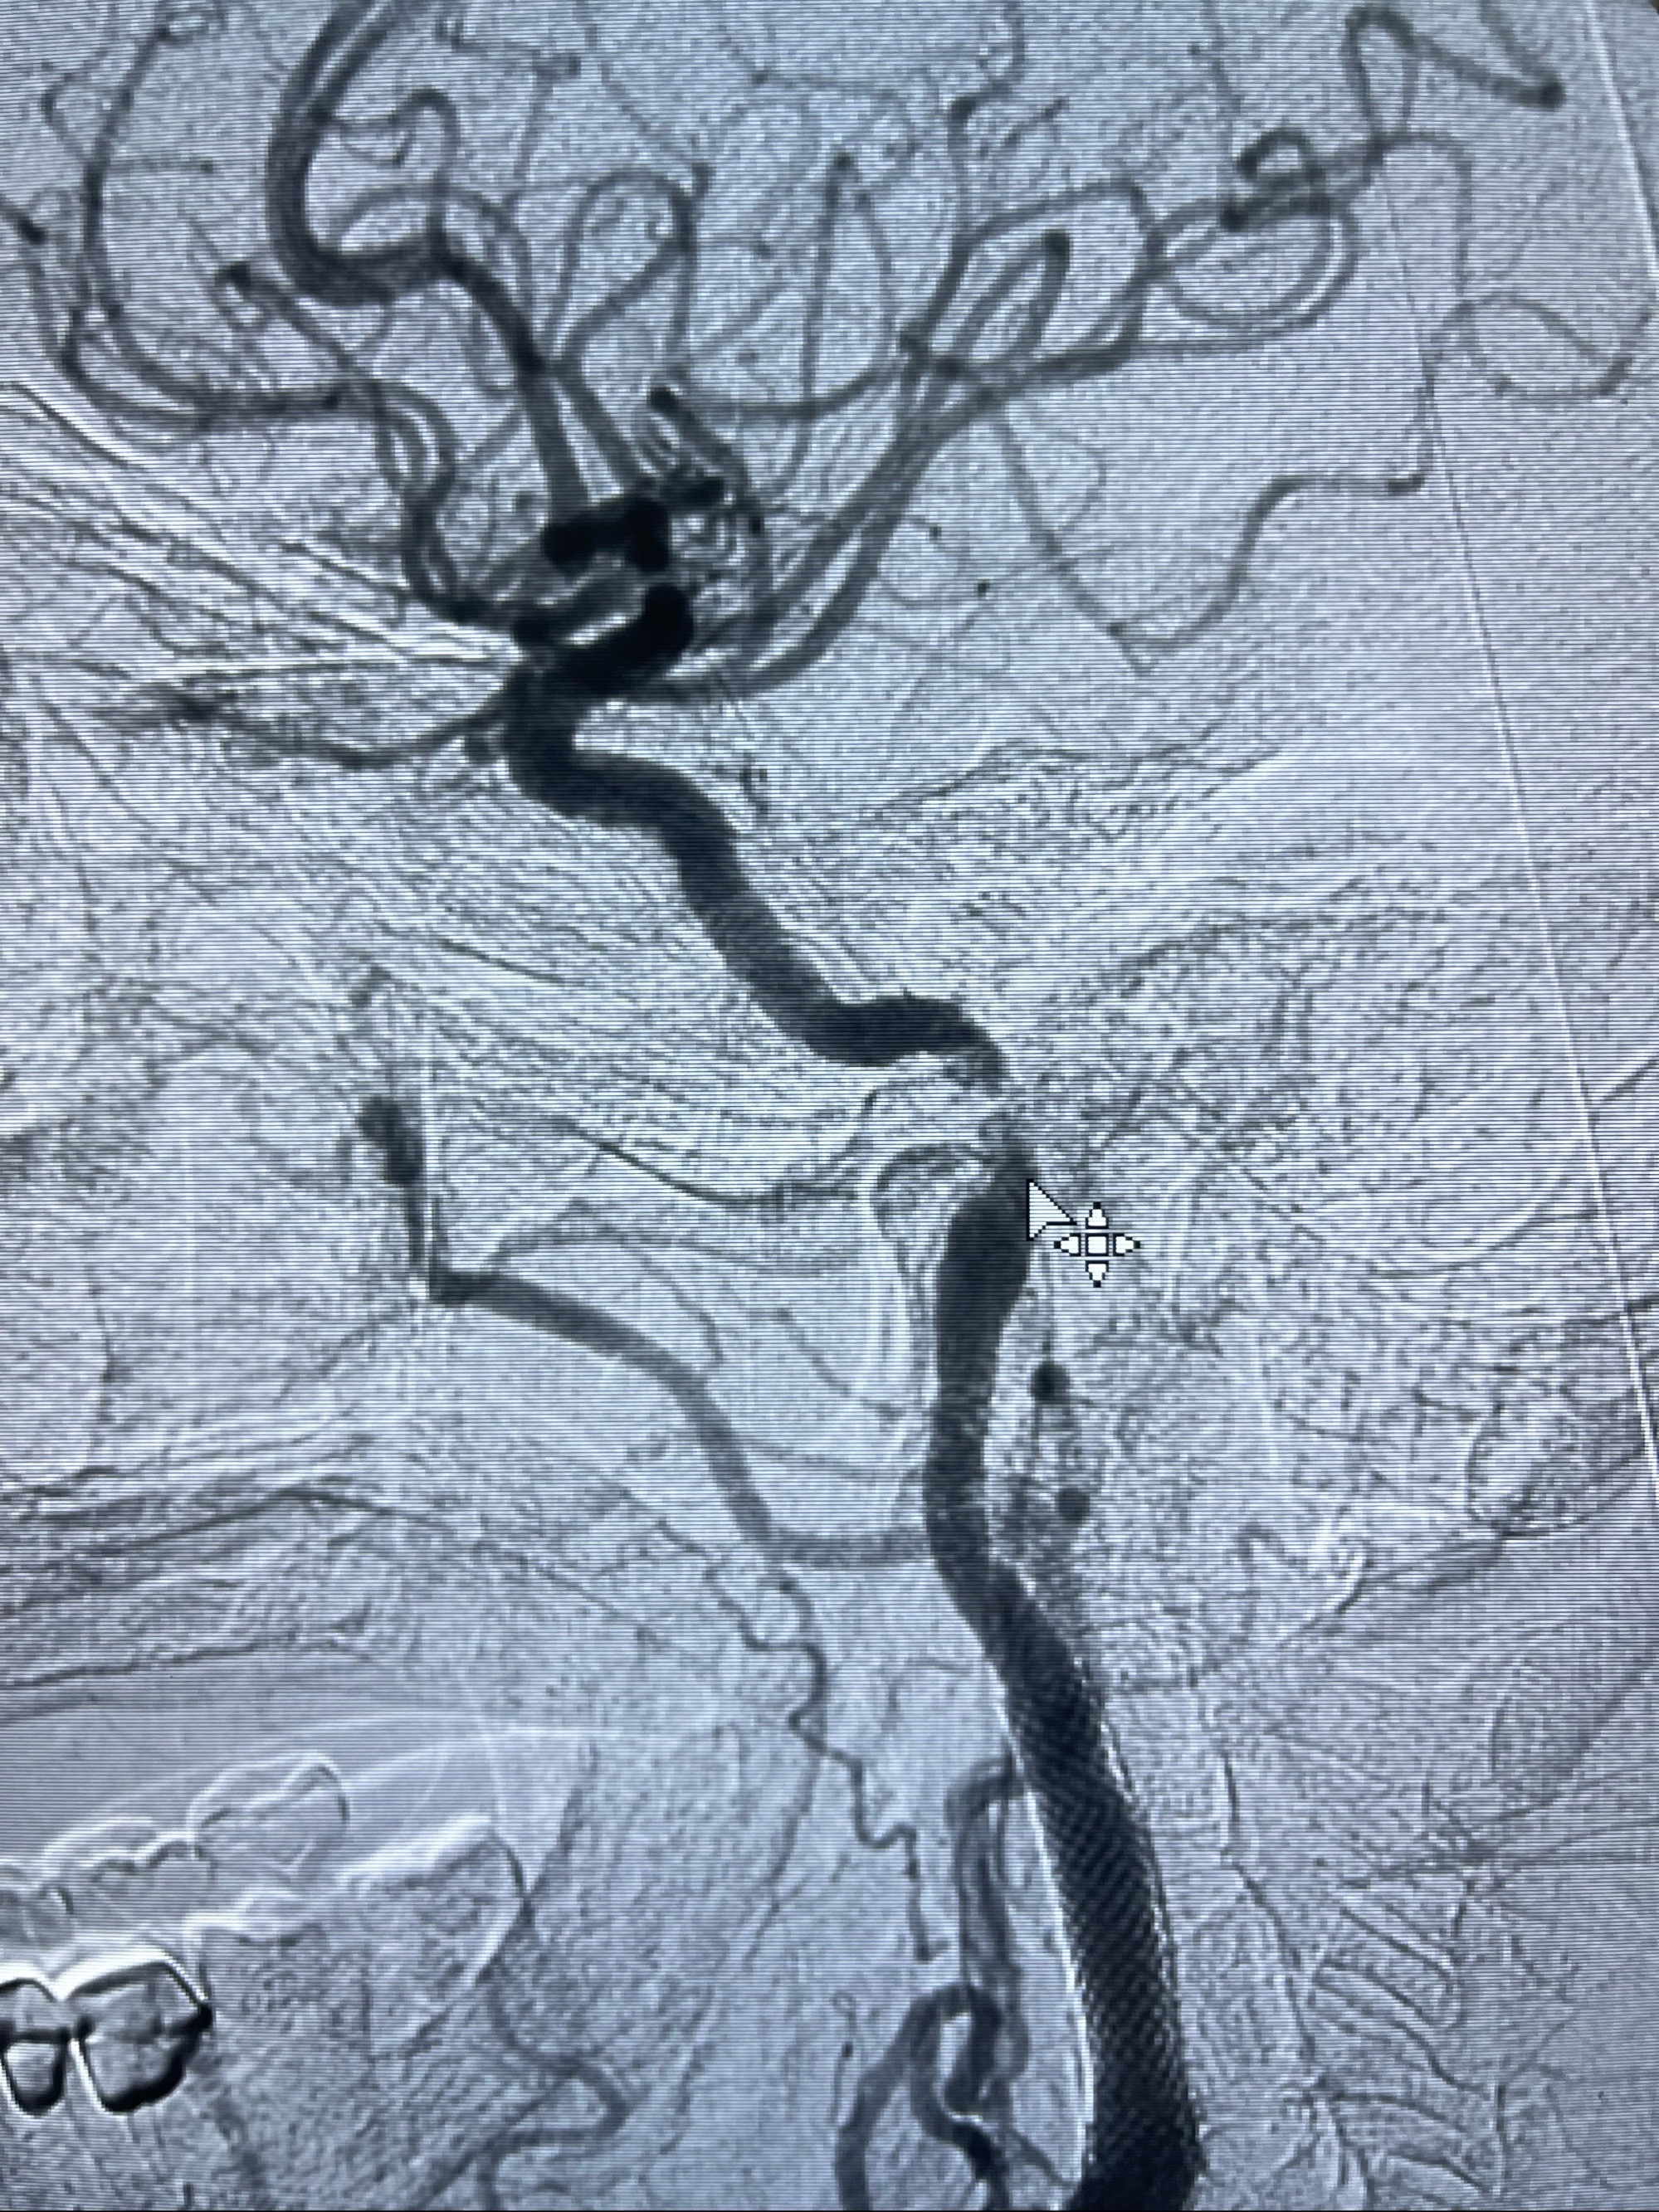

2023-07-10DSA:右侧颈内动脉岩骨段夹层伴中偏重度狭窄改变,左侧颈总动脉闭塞、右侧颈外动脉由右侧肋颈干甲颈干吻合代偿

右侧椎动脉可见吻合代偿右侧颈外动脉

左侧颈总动脉起始段至分叉部闭塞,起始部呈现子弹头样改变

左侧椎动脉可见代偿显示左侧前循环